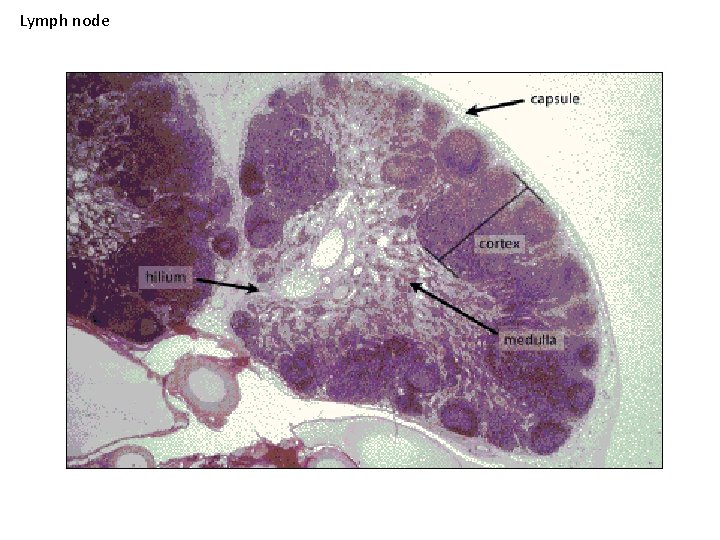

Lymph node Cortex Capsule Medulla Capsule Trabecular C. T. + blood vessels

Lymph node

Subcapsular sinuses Afferent lymphatics Capsule

Medullary cords Medullary sinuses